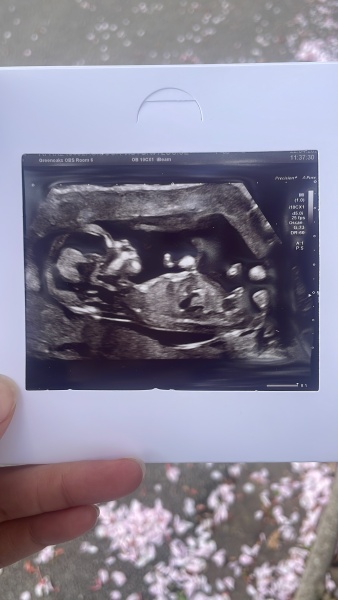

RavensMom24 · 01/05/2025 10:30

Hi ladies! Hope everyone is doing well in this heat!!

Just a quick one - I’m having my gender scan this afternoon so I will come back and update soon. I don’t think I posted a scan pic at the time so I’ve attached one now - we’re thinking boy but absolutely happy with either. So excited!!

@RavensMom24 definitely a little boy!

RavensMom24 · 01/05/2025 15:09

Update - @emmatcc1 you were absolutely right - we’re having a boy!!😊💙 He wasn’t shy about showing us either! 😂🙈

We already have our daughter who’s 13 months so we will be one of each, approx 19 months apart.

Should be fun and games for a few years🤣 but we’re looking forward to it! lol Now to think of a name lol! x